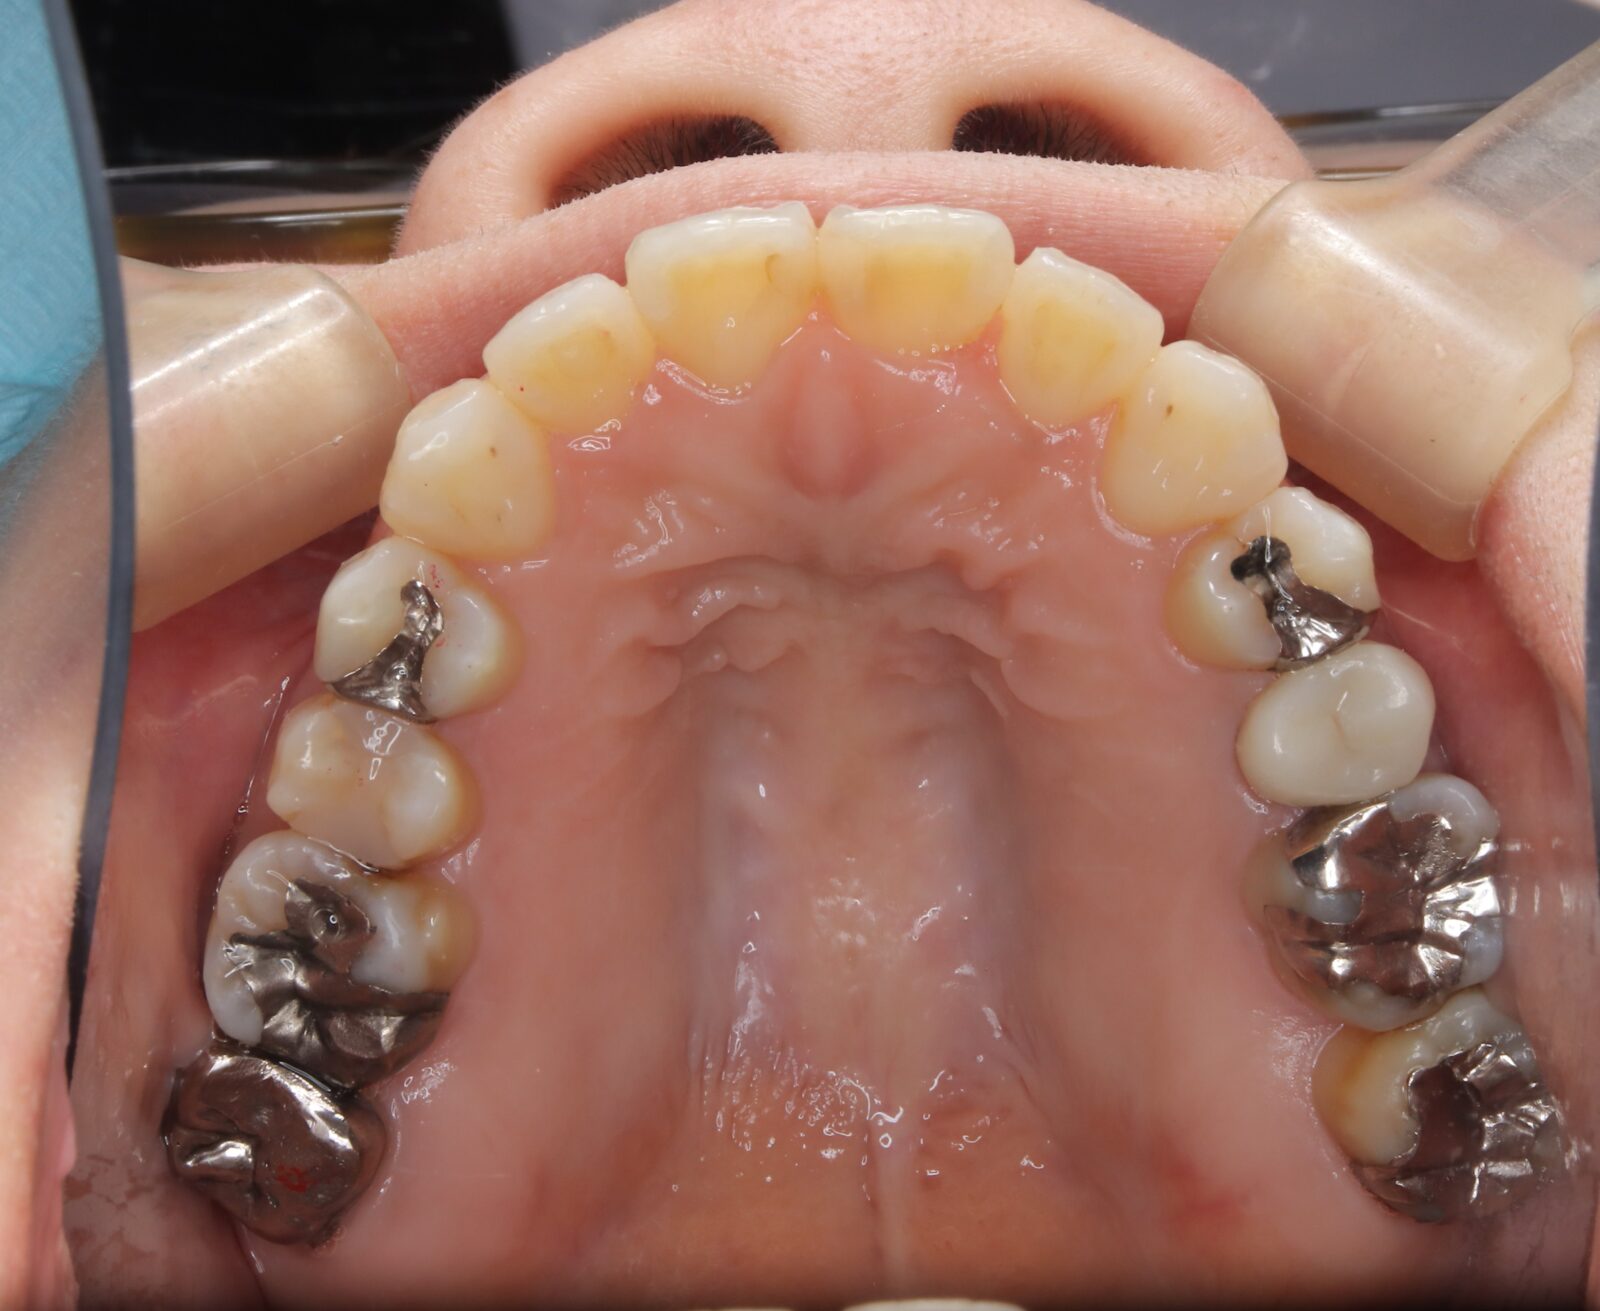

矯正と補綴が必要で実施した症例

左側に隙間。歯の数が少ない。もともと2番と7番がない。(先天欠如)歯の数が少ないため上顎のアーチ全体が小さい。歯槽骨の幅も狭く、歯肉も薄い。骨質も弱かった。

上顎左右2番と6番が先天欠如。下顎左右1番も先天欠如でもともとブリッジが装着されていた。

左右非対称なすきっ歯。上顎の前歯がないので左側の隙間を左右2番相当部に集めた。

上下の前歯が反対の噛み合わせ(受け口)で、干渉しているためうまく閉じることができず、奥歯は左右同時に噛めないので、どこかにずらさないと口を閉じられない。

左右の歯を同時に合わせることができず、どこで噛んだら良いかわからない噛み合わせでした。

小臼歯部は噛み合うことがない側方の開口状態。矯正と補綴が必要なケース。 主訴は顎の不調と歯軋り、夜間の食いしばり。

マルチブラケットとインビザラインを併用し、クラウンとブリッジを装着しました。

上顎左右2番は、歯が入るスペースを作り、ブリッジを装着しました。

他の歯医者で何軒も断られていました。 骨の幅がうすくインプラントはできない。骨の質も柔らかい。PCR検査の結果も歯周病ハイリスク患者でした。

歯の位置は、本人の顎が安定する場所を探して着地した。 左右で噛み合わせが非対称で、理想的な歯のポジションを獲得できなかったものの、左右同時に噛むことができるようになった。

顎関節の症状も落ち着いて、開口障害や、顎の痛みは無くなった。

矯正治療はどの装置を選択しても歯周病のリスクを高めてしまう。

これ以上の歯の移動が歯周病と骨質、骨の代謝のバランスの兼ね合いで困難であると判断し、ここが着地点とした。